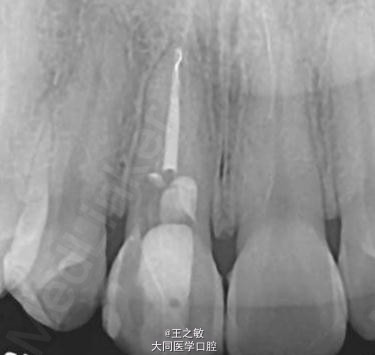

患者男,28岁 主诉:牙根裸露牙龈不齐 病史:过去根管医师用MTA修补穿孔区后,转诊寻求牙根覆盖术治疗

行牙龈移植术 处理:信封法撑开,根向深度5毫米,腭侧取结缔组织移植,把结缔组织当成信纸放入,使用可吸收线在近远中两侧做褥式缝合固定